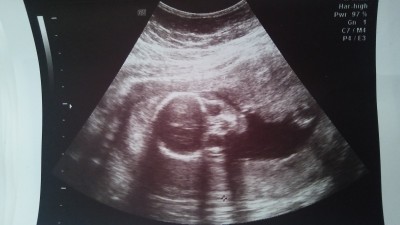

göz kısmının altında sagda yoksa ultrason kaynaklımıdır şimdi incelerken fark ettim

Gebelik haftası 19

Allah aşkına abartmayın siyah beyaz ultrason kağıdında nasıl bir leke ye benzetme yapiyorsunuz bebeğin tam organları bile olusmamisken vallahi pes diyorum

canim ultrasonda bu tür seyleri farketmek imkansız çünkü ses dalgalariyla olusan bi cihaz ve bebek suyun icinde yasiyor zaten doğru düzgün bise de belli degil doktorlar bir kac önemli yerlerine bakiyor sadece bu tür şeyleri kafana takma gamze olsada olmasa da önemli olan bebeğinin sağlığı

CNM o gölge daha tam gelişmemiş bile bebeginiz endişe etmeyin leke olsa bile anlaşılmaz

Detaylı ultrasonda yüzünün resmini verse bir ihtimal görebilirsin diyicem ama buradan anlaşılmaz.

O gördüğünüz yüzü bile değil. O kadar büyük kafa mı olur. Ultrasonda böyle şeyler görülmez zaten doğmadan hiç bisey net ve garanti olmaz rahat olun bence.

Gamze şimdi olmaz, leke de değil. Ultrason her noktayı algılamıyor. İlerleyen haftalarda daha tuhaf görüntüler de olacak :) olumsuz bişey gelmesin aklına

Yalnız o yüzü değil ki zaten şuan yüzü bile tam oturmamıştır ne lekesi ?

Doğum yaklaşacaginda 4 boyutlu çekimlerde bile görünmez böyle birşey siz 19 haftada nerde gördünüz yüzündeki lekeyi

Bebekler hiç bir zaman yüzüne ultrasyona tam olarak bu şekil dönmezler birde daha 19.hafta takma kafana canım leke de olsa gamzede olsa sağlıklı olsun yeterli